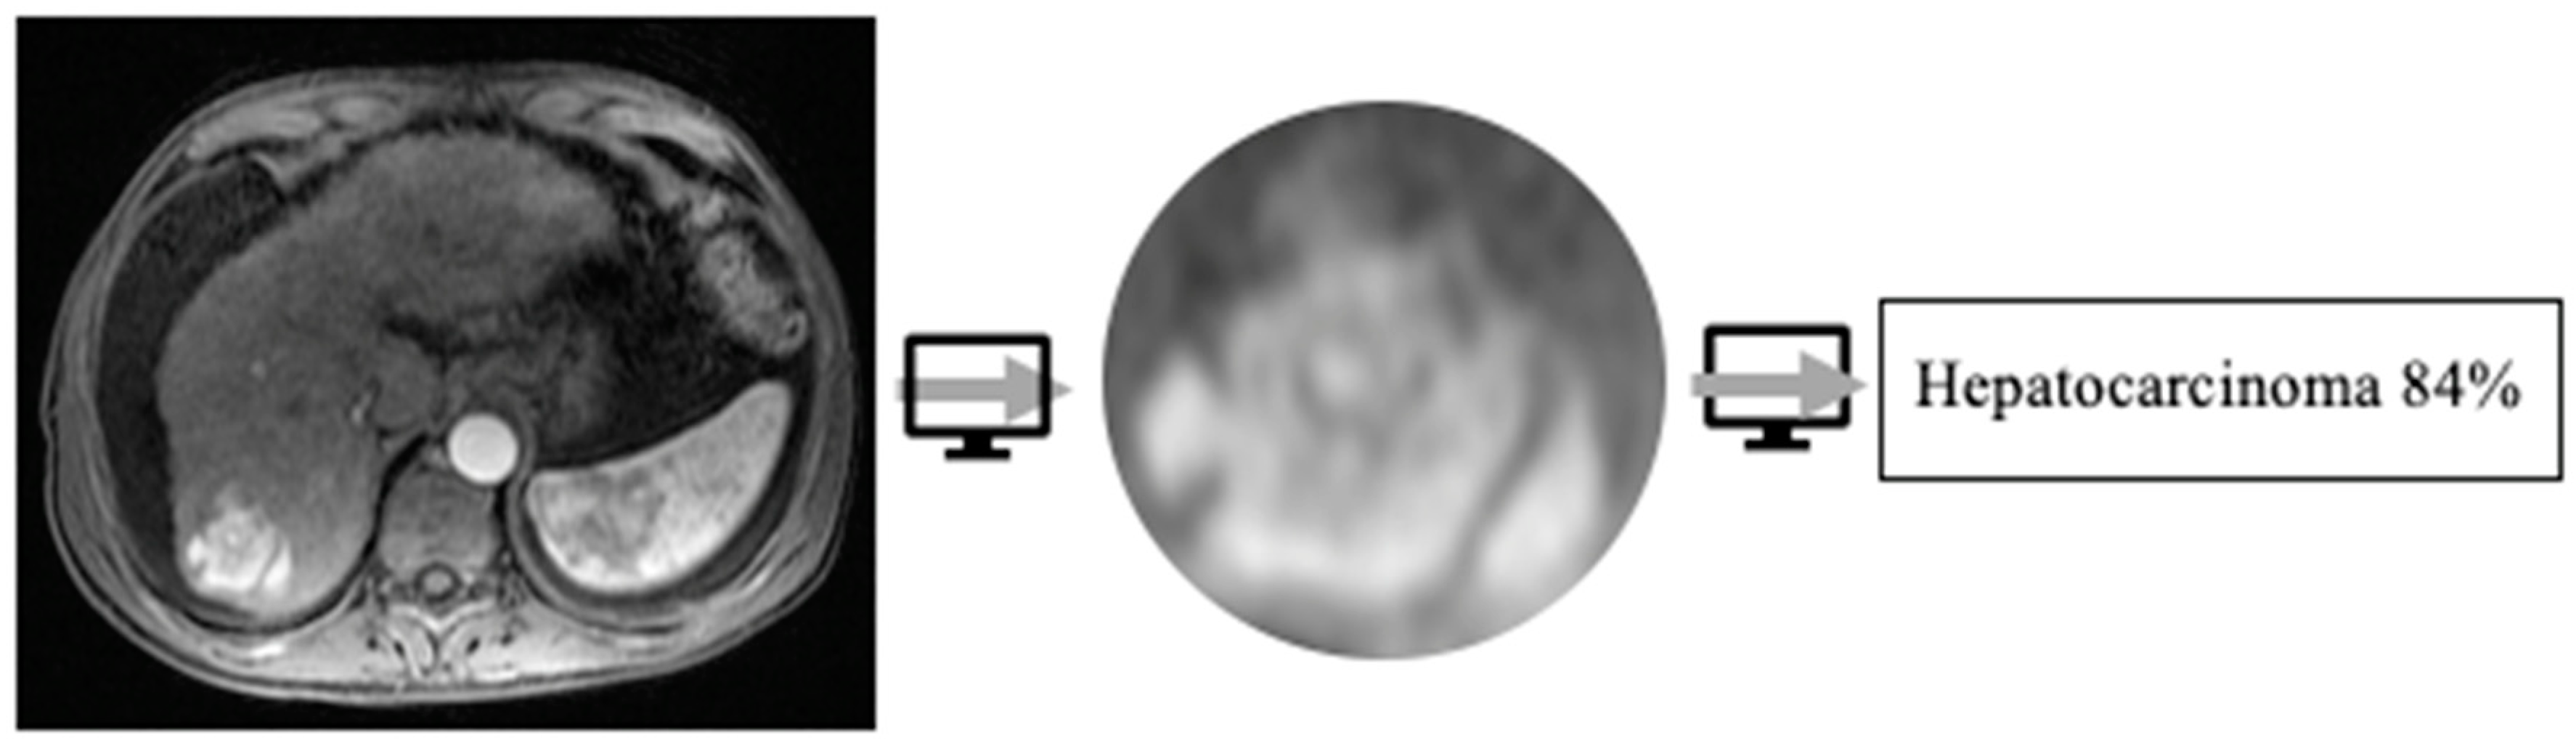

- Kim, J.; Min, J.H.; Kim, S.K.; Shin, S.Y.; Lee, M.W. Detection of hepatocellular carcinoma in contrast-enhanced magnetic resonance imaging using deep learning classifier: a multi-center retrospective study. Scientific reports 2020, 10, 1–11. [Google Scholar] [CrossRef]

- Bousabarah, K.; Letzen, B.; Tefera, J.; Savic, L.; Schobert, I.; Schlachter, T.; Lin, M. Automated detection and delineation of hepatocellular carcinoma on multiphasic contrast-enhanced MRI using deep learning. Abdominal Radiology 2021, 46, 216–225. [Google Scholar] [CrossRef] [PubMed]